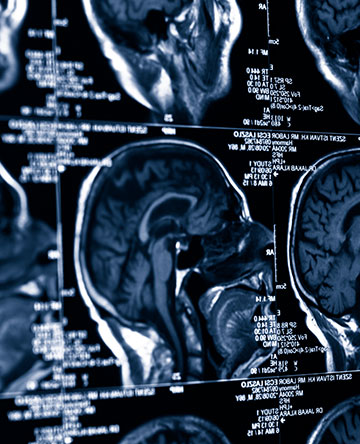

One of the key ways to determine an athlete’s brain recovery following a concussion is to compare the level of brain function before and after the concussion.

At the Wellington Sports Concussion Management Program, we use ImPACT©, a research-based software program that evaluates multiple aspects of brain function, such as memory and mental processing speed. The information we gather can help us to assess how severe the concussion is and to monitor recovery of brain function.

ImPACT© provides important insights into the challenging puzzle of concussion management for athletes from middle school through college. It can help us return these young athletes to play as quickly and safely as possible following a sports concussion.